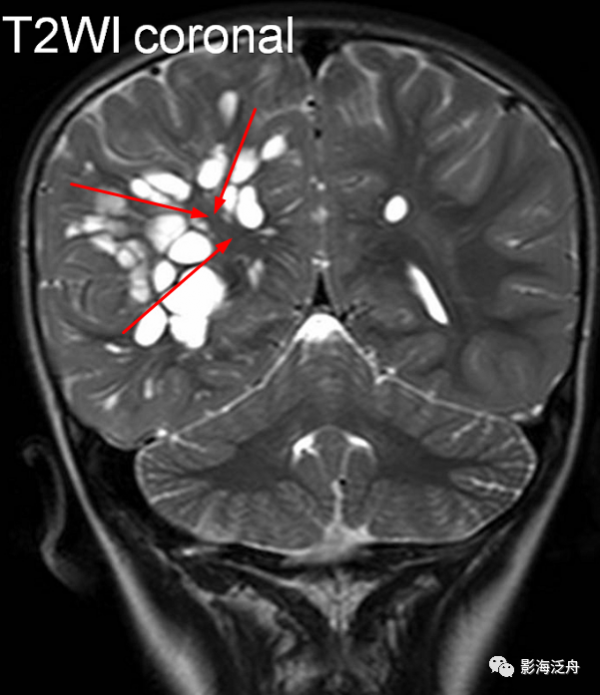

左側基底節區腔梗灶,病灶既不像類圓形也不像規則的長條狀,在Flair序列上灶周可以看到淡淡的高訊號影(紅箭)。基底節區的腔梗灶位置相較於擴大VR腔隙往往更加靠近上份層面、形態不規則,且隨著病程時間延長Flair序列高訊號會愈加明顯。

![]()

左側基底節區腔梗灶(紅箭頭),儘管後部的那個病灶看起來有點圓,但在Flair序列病灶周圍可以看到非常明顯的高訊號(綠箭),代表區域性膠質增生,證明其為慢性期腔梗灶而非擴大的VR腔隙,其餘病變(黃箭)為對稱性分佈,呈斑點狀或長條狀,Flair序列灶周無高訊號,診斷VR腔隙更為合理。